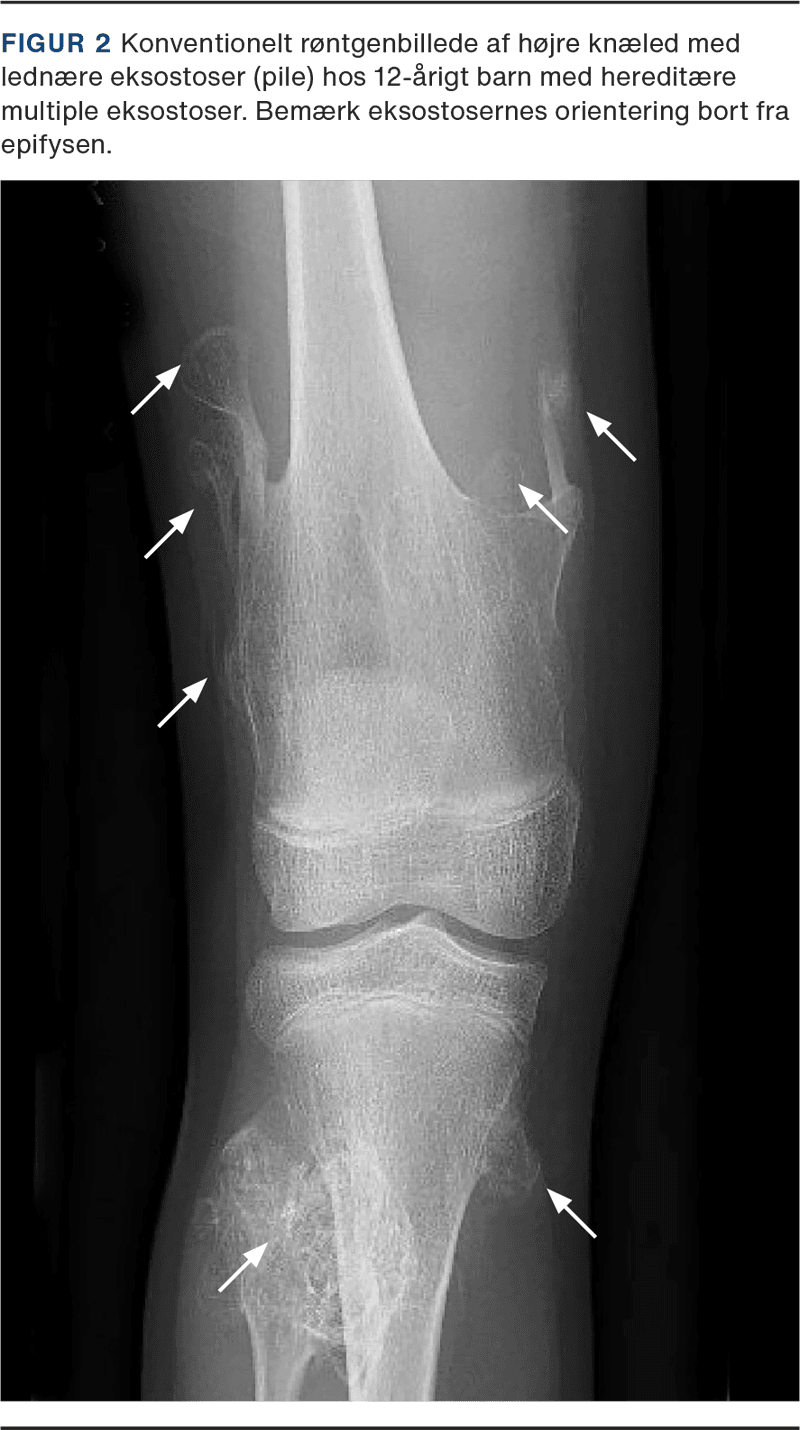

Grundig anamnese og klinisk undersøgelse er essentiel for at få fastlagt diagnosen. I Danmark anvendes primært konventionel røntgenundersøgelse til diagnostik og løbende kontroller hos børn (Figur 2), og voksne følges med MR-skanning, som giver billeder i højere kvalitet. Røntgenundersøgelser er kortvarige og sufficiente til påvisning af eksostoser på ekstremiteter, men udgør en strålerisiko hos de børn, der ofte kontrolleres [29]. MR-skanning er fordelagtig til diagnostik af centrale eksostoser samt tumordiagnostik. Dansk forskning af Jurik et al [17] har undersøgt, om årlig helkropsskanning med MR bør tilbydes som screeningsværktøj til patienter med HME. I studiet, der inkluderede 57 patienter med HME, udvikledes kondrosarkomer, hvoraf ti var på truncus og en enkelt på proksimale tibia. I studiet konkluderes det, at helkrops-MR-skanning potentielt kan anvendes til årlig screening, idet kondrosarkomer kan påvises inden symptomdebut. Alternativt kan foretages reduceret helkrops-MR-skanning af truncus, skulderbæltet samt proksimale femur enten årligt eller hvert andet år hos patienter uden tidligere kondrosarkom. Dertil kommer, at patienterne bør informeres om malignitetstegn for at sikre tidlig diagnostik på de dele af skelettet, som ikke medskannes. Bedre videnskabelige undersøgelser er dog påkrævet for at kunne udtale sig om effektivitet og omkostninger ved systematisk MR-skanning til denne patientgruppe. Studiet af Jurik et al [17] danner i dag grundlag for den nationale retningslinje for opfølgning af patienter med HME, men der er behov for yderligere forskning inden for udredning og opfølgning.

Eksostoser består af knogle dækket af bruskkappe og orienterer sig væk fra epifysen. De opdeles i to hovedtyper: pedunkulære og sessile. Nogle eksostoser vil umiddelbart observeres eller identificeres ved palpation grundet deres størrelse, og mindre eksostoser diagnosticeres med billeddiagnostik [2]. Arvegangen er autosomal dominant og skyldes oftest en patogen variant af generne for exostosin: EXT1, EXT2 eller EXT3 [1, 3]. Den estimerede prævalens i vestlige lande er 1:50.000 [1], men den præcise prævalens er ukendt, idet asymptomatiske individer udgør et mørketal [4]. Forskning tyder på, at sygdom forårsaget af den patogene EXT1-variant er forbundet med højere symptombyrde end EXT2-varianten. EXT3-varianten er fundet senere end EXT1 og EXT2 og er derfor ikke undersøgt i samme omfang endnu. Hos 5-35% af patienterne finder man hverken mutation i EXT1 eller EXT2 [1]. I sådanne tilfælde er ætiologien uafklaret, men den kan skyldes mutation i EXT3 eller have genese i somatisk mosaicisme [5].